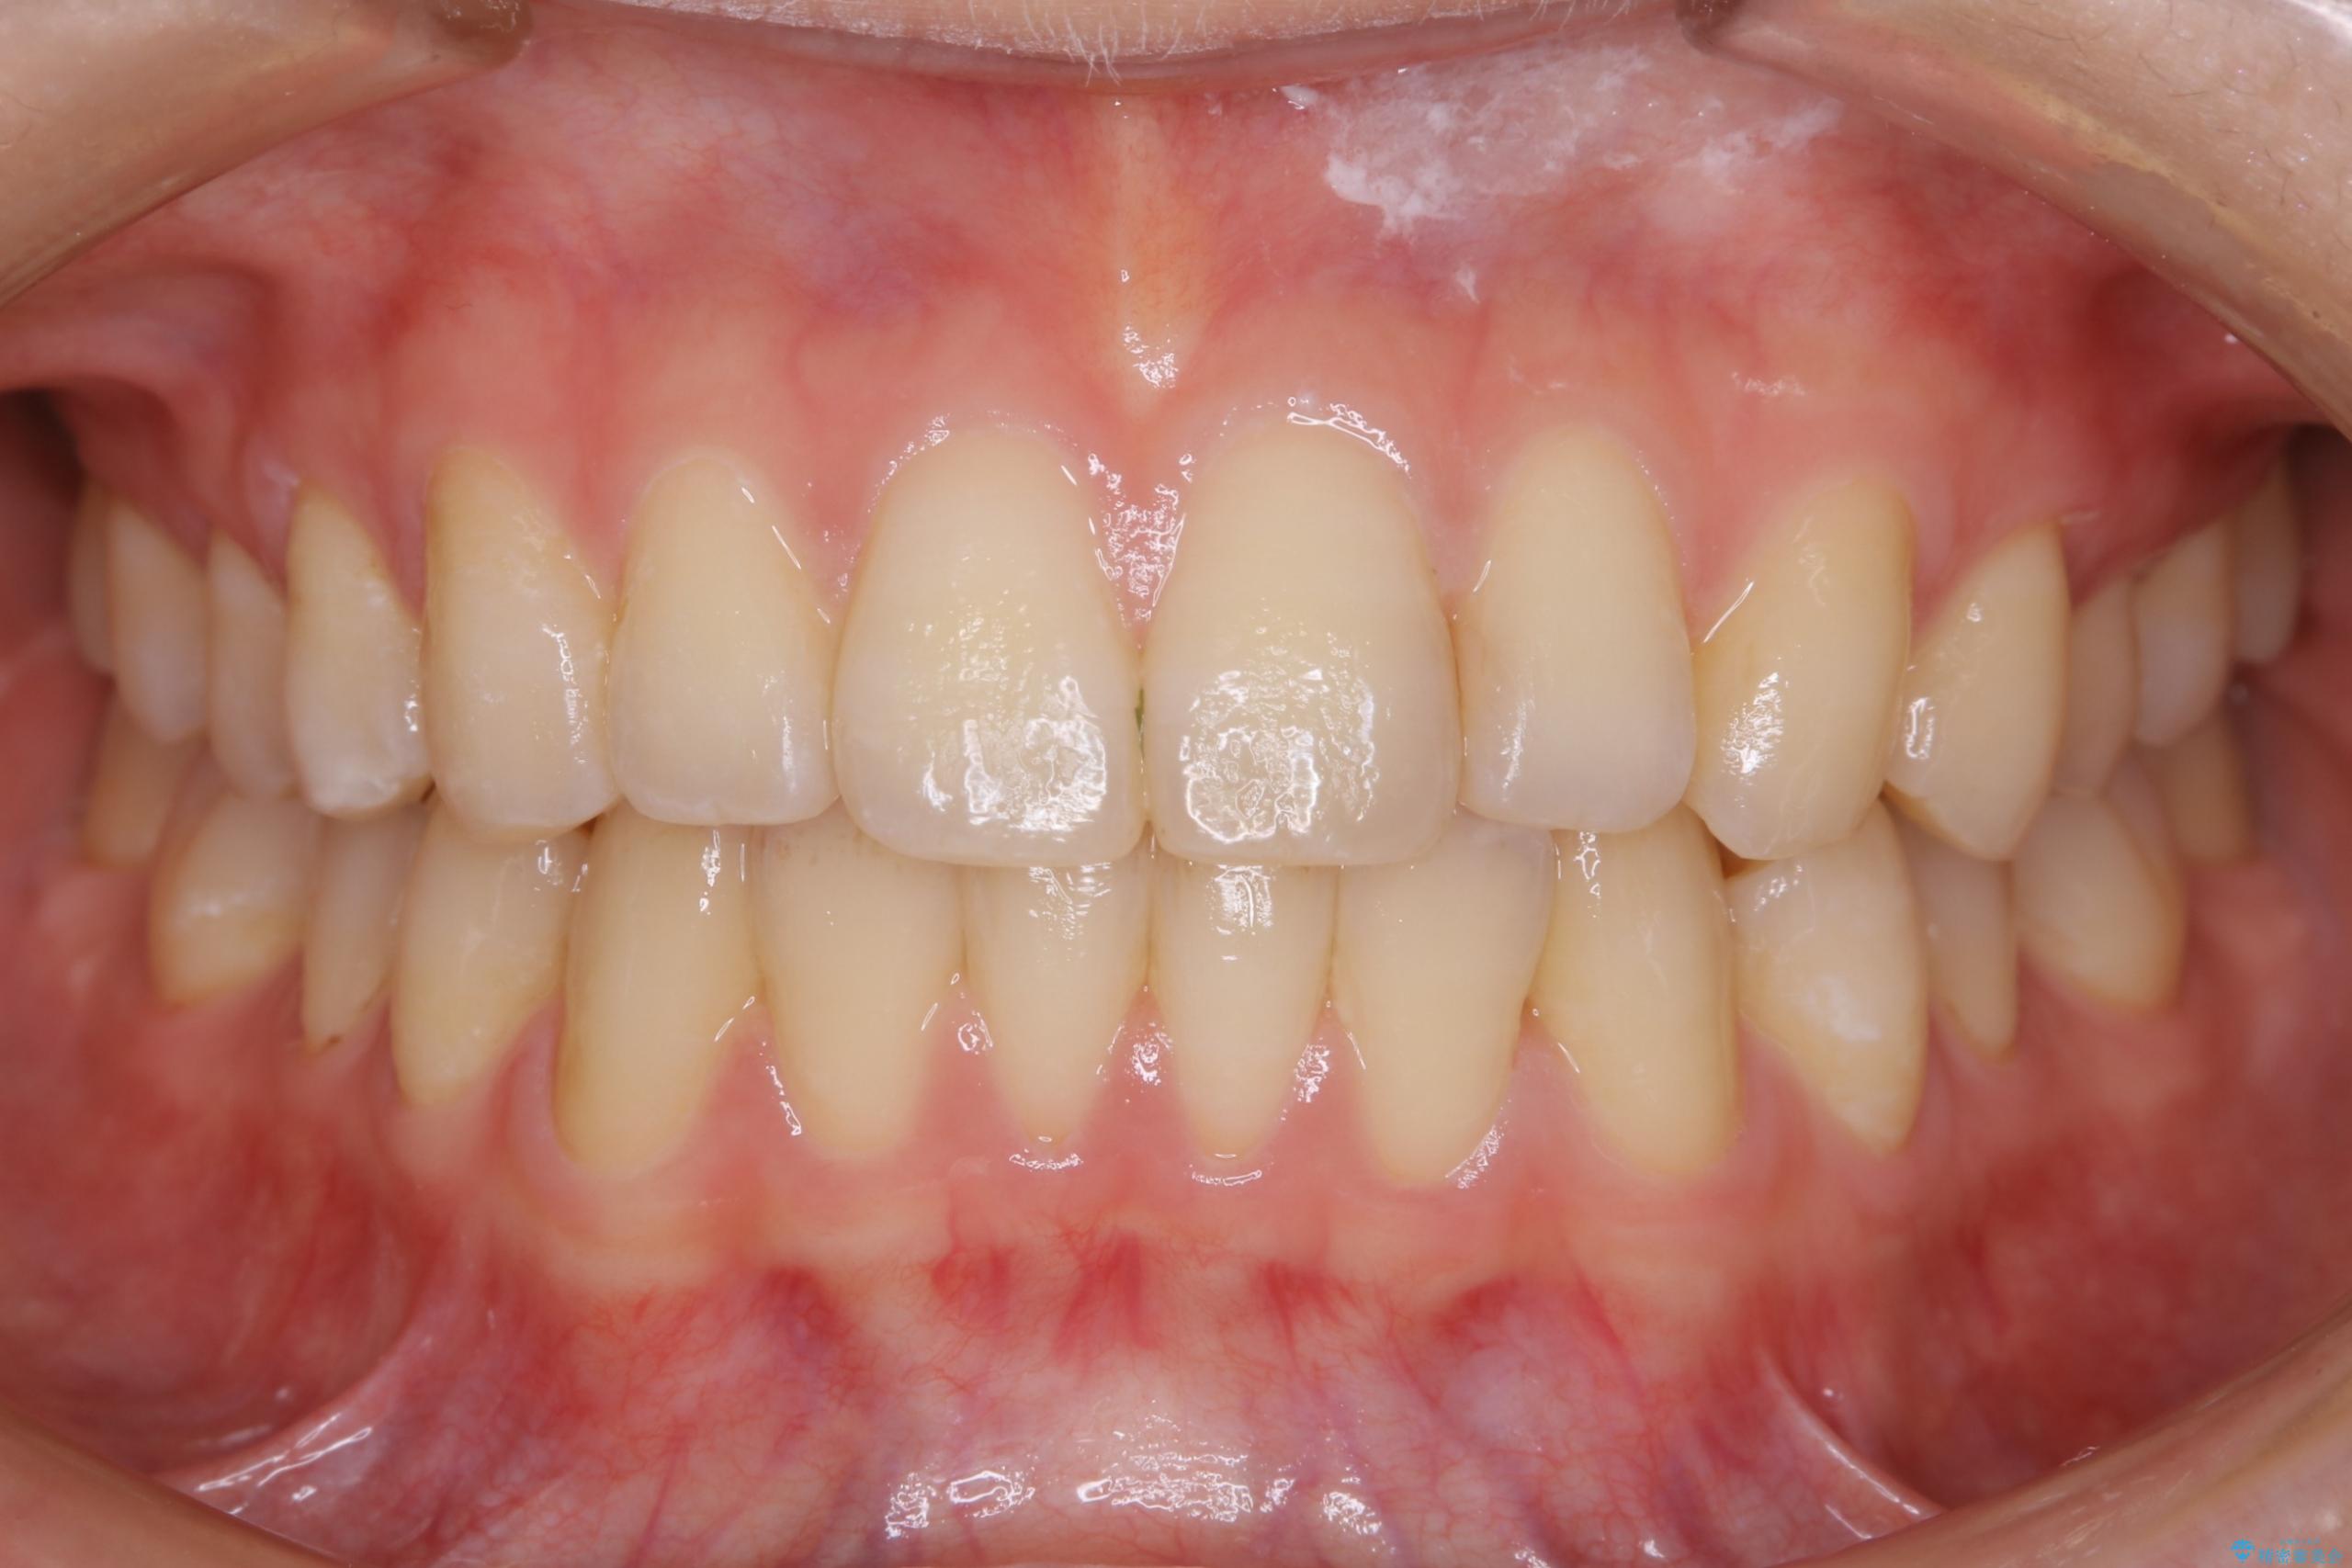

ディスキング(IPR)

歯のガタつきをとるためのスペース作りの方法の一つにディスキング(IPR)という方法があります。

歯と歯の間を一ケ所あたり最大0.5mmまでの範囲内で削ることで歯自体が少し小さくなり、それにより作られるスペースを数ヶ所分合わせることで合計で数mmの大きなスペースが作れるという方法です。

当院ではなるべく歯の機能や見た目に影響の出ないよう、作業時に拡大鏡の使用や削るタイミングの微調整を行っています。